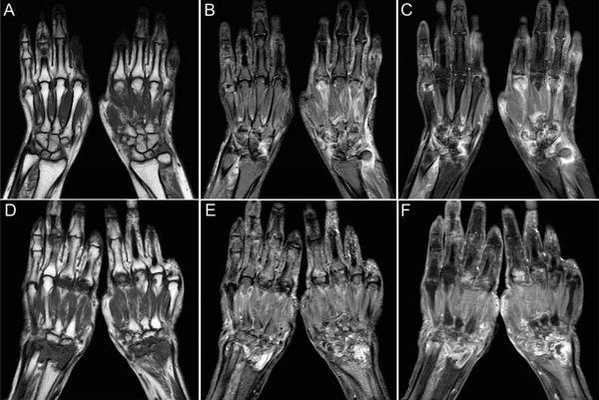

Ревматоидный артрит поражает людей молодого возраста. Начинаются симптомы с мелких суставов кистей рук, стоп. МРТ руки следует сделать, так как можно заметить минимальные изменения в суставах: неровность контуров хряща, сужение щели или наоборот, выпот внутри сустава. Такие изменения вместе с лабораторными признаками позволяют поставить диагноз и начать лечение, пока больной не испытывает сильных болей, скованности, большинство суставов имеют нормальную структуру. Раннее лечение значительно улучшает качество жизни таких больных, предупреждает наступление множественных деформаций суставов и инвалидности.

МРТ тоже видит ткани в виде срезов в заданной плоскости. При КТ и МРТ возможна реконструкция снимков в трехмерное изображение для наглядности и простоты диагностики. МРТ показывает кровеносные сосуды, нервы, мышцы, сухожилия, апоневрозы, суставы, кости, кожу и подкожно-жировую клетчатку. Исследование считается более информативным по сравнению с КТ, когда дело касается мягких тканей. Также оно намного более безопасное.